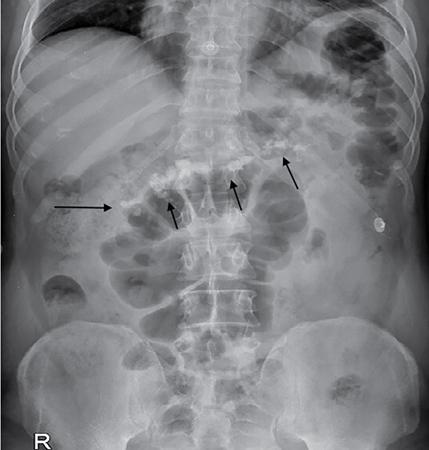

Samarjit Ghuman, Seema Sud, Deeksha Rastogi, Swapnil Sheth, T.B.S. Buxi PLAIN RADIOGRAPHY FOR HEPATOBILIARY IMAGING The diagnostic imaging techniques for hepatobiliary imaging can be intimidating with many techniques/modalities providing the information desired. The job of the diagnostic radiologist includes being familiar with the available choices and pick the ‘best fit’ keeping in mind the pros and cons of each modality, which includes plain X rays, Contrast studies using plain X rays and fluoroscopy, Ultrasound includiojng Doppler and Ultrasound elsastography, CT including multiphase CT and MRI and MRI elastography. Understanding the strengths and weaknesses of every modality as well as the ability to tailor each study individually will help to optimise patient cares. The abdominal radiograph is performed almost exclusively in the supine position and in the AP (anteroposterior) projection. In case of acute abdomen, an erect chest radiograph should also be performed to look for free air under the diaphragm. The standard abdominal radiograph should extend from the diaphragm to the inferior pubic rami, and includes the lateral abdominal wall musculature. Routinely no preparation is required for abdomen radiograph done for hepatobiliary imaging. The radiograph has limited soft-tissue contrast, however, the liver being the largest intra-abdominal organ, casts a perceptible shadow. The margins of the liver can indirectly be seen by outline of adjacent organs like lung, hemidiaphragm, pro-peritoneal fat line, kidney and gas shadows of stomach/colon. The right lobe is seen better than the left lobe of liver. The following pathologies may be visualized on the plain radiograph of the liver. Liver enlargement Liver mass Calcification Increased radiodensity of the liver Decreased radiodensity of the liver An ultrasound is the first line investigation; however, a radiograph may be done for routine evaluation of abdominal pain. The following pathologies may be seen on plain radiograph of the biliary tree. Calculi and Calcifications Gas ULTRASOUND OF HEPATOBILIARY SYSTEM Ultrasonography (USG) is the initial imaging modality of choice for scanning hepatobiliary system. USG is accurate and has high sensitivity and specificity in diagnosing biliary pathologies. Table 9.1.1 shows indications of ultrasound in hepatobiliary system. The real-time nature of ultrasound lends itself to demonstrate mobility of calculi and sludge and the sonographic Murphy sign can easily be elicited during scanning. The main disadvantage is operator dependence, patient’s body habitus, presence of gas which can obscure the visualization of organs, overlying bandages in a postoperative patient and incomplete evaluation in a nonfasting state. USG of upper abdomen should be done after 6–8 hours of overnight fasting. Milk and fatty food should be avoided as they cause contraction of the GB and may cause the GB walls to appear thickened. History of previous surgery, especially cholecystectomy should be elicited. The patient may be positioned in supine or left lateral decubitus position. The GB can be scanned from a high/lateral view, looking through the ribs in supine position or through a sub-costal view in left lateral decubitus position. Position of patient may be changed to demonstrate mobility of structures. The GB is an anechoic structure which is located in the GB fossa along the posterior and inferior aspect of the liver. It has a fundus, body and a neck. It should always be examined in at least two planes (Fig. 9.1.6A and B). The wall of the normal GB should measure 3 mm or less and pathological GB wall thickening can be due to cholecystitis or a neoplastic aetiology. Calculi appear as mobile hyperechoic foci, with distal acoustic shadowing. Other pathologies include polyps and sludge which can be differentiated on the basis of their mobility. The CBD measures less than 6 mm in diameter with increase in the diameter with patient’s age and after cholecystectomy. The CBD is usually scanned in an oblique subcostal plane with the patient in the left decubitus position (Fig. 9.1.7). Dilatation of the intrahepatic biliary radicles is readily assessed with USG and normal intrahepatic biliary radicles are usually not appreciated on USG. Ultrasound of the liver, broadly, is done to assess the size, surface (smooth, coarse or lobulated) parenchymal echogenicity (increased or decreased) vascularity and for presence and evaluation of intrahepatic masses or fluid collections. The liver is divided into right and left lobes by plane of middle hepatic vein which passes through GB fossa and notch of IVC (Cantlie Line). Couinauds classification is the most commonly used system for liver segmental anatomy and described liver into eight functional segments. It is based on distribution of portal and hepatic veins. Every segment has its branch from portal vein, hepatic artery and bile duct (Fig. 9.1.8). Curvilinear transducer (3–5 MHz) is used for routine examination of liver and GB (Fig. 9.1.9). A high-frequency linear transducer (9–11 MHz) (Fig. 9.1.10) can be used to look for subtle irregularity of the liver surface for early Cirrhosis and fine details of GB wall. The liver is scanned in deep inspiration, which causes inferior movement of liver, so that superior borders of the liver are well visualized. Supine position is used for the size of the liver. The measurement is made in sagittal mid clavicular position on right side, in craniocaudal dimension. It is taken from diaphragm to the lower end of the liver. It should be <16 cm and varies with age and sex. The liver is divided into four vertical sectors by three hepatic veins and plane of bifurcation of portal vein divides these 4 sectors in to 8 segments. The right hepatic vein creates vertical plane in the right lobe separating segments V and VIII (anterior) from VI and VII (posterior). The portal vein bifurcation creates a transverse plane and divides these segments into superior (VII, VIII) and inferior segments (V, VI). The left hepatic vein divides the left lobe into medial (IVa, IVb) and lateral sectors (II, III). The left portal vein divides left lobe into superior (Iva, II) and inferior segments (III, IVb). The middle hepatic vein separates medial segments of left lobe (IVa, IVb) from anterior segments of right lobe (V, VIII). Ligamentum teres separates segment III from IVb. Ligamentum venosum separates segment I from IV and II. Cystic duct is an anechoic tubular structure which connects neck of the GB to the extrahepatic biliary tree. In long axis view of GB, the neck of the GB is related to main lobar fissure which appears as a linear echogenic line which runs obliquely between neck of GB and right portal vein. In the right oblique sub coastal view CBD is seen anterior and parallel to portal vein. A series of standardized sections or views may be obtained for liver scanning. Transverse Subcostal View: In this view the probe is angled cephalic and placed transversely under the ribs on the right side and portions both lobes of the liver can be seen (Fig. 9.1.11). Mid Transverse View (Fig. 9.1.12) in this transducer is kept in transverse plane in the midline below the xiphisternum. It visualises the liver in an inferior to superior transverse oblique plane and portions of both lobes of liver can be seen along with right and left portal veins. This view is obtained by angling the transducer superiorly toward the hepatic venous confluence. In this view, we can see the three hepatic veins joining the IVC. Right Parasagittal View for Both Right Lobe and Kidney: This view allows assessment of inferior right lobe of liver. It also allows assessment of relative echogenicity of liver and renal cortex as both are seen together in the same image. Normal liver parenchymal echogenicity is greater than renal cortex and less that renal medulla (Fig. 9.1.14). Parasagittal Right MidClavicular View: In this transducer is kept in sagittal plane in right midclavicular line, and oriented supero-inferiorly. This is the standard view for assessing craniocaudal span of liver (Fig. 9.1.15). Parasagittal View for the Left Lobe: For evaluation of left lobe of liver and lateral segments (2 and 3) (Fig. 9.1.16). This view is obtained along the direction of the main portal vein. CEUS of the liver is done to evaluate Focal Liver Lesions and complements traditional B mode ultrasound and Doppler study. It is a simple, accurate and cost-effective tool complimenting indeterminate CT and MRI findings or for characterization of lesions in patients who cannot receive CT/MRI contrast and can be used in patients with compromised renal function, with minuscule risk of side effects. As CEUS is real-time, microvasculature can be studied along with tissue perfusion kinetics. Indications and uses of CEUS: Contrast agents and technique: Interpretation: Contrast-enhanced ultrasound of a hepatic hemangioma in different phases (Fig. 9.1.19). Limitations of CEUS: Liver elastography is a noninvasive method for diagnosing liver fibrosis. Liver fibrosis is induced by chronic liver disease leading to cirrhosis and liver cancer. Liver biopsy is the gold standard for diagnosing the degree of fibrosis and for staging but it is an invasive method. Elastography helps in analysing the elasticity or the stiffness of the tissue. A stiffer liver tissue indicates fibrosis or chronic liver disease. ARFI is based on the principle of measuring Shear wave velocity. Short duration acoustic pulses which are generated in the tissue and these give rise to shear waves which travel, perpendicular to the ultrasound beam. These shear waves cause tissue displacement followed by recovery. This displacement and recovery depend on tissue stiffness. To monitor these shear waves US beams of low intensity are emitted continuously parallel to the main beam along with the push pulses, and these beams can gather data regarding the tissue stiffness. The shear waves cause tissue displacement and this tissue then recovers from the impulse. From this data the degree of tissue stiffness can be obtained which is displayed either as a map or quantitatively where tissue elasticity is expressed as shear wave velocity measured in meters per second. F0, normal; F1, enlarged fibrotic portal tract; F2, periportal/initial porto-portal septa with intact architecture; F3, architectural distortion with no obvious cirrhosis; F4, cirrhosis. It is also known as Transient Elastography (TE) and works on the similar principle as ARFI, the difference being that B mode ultrasound image is not produced. DOPPLER OF PORTAL VEIN The portal vein divides at the portahepatis into right and left branches. The right portal vein divides into anterior and posterior branches, and the left portal vein divides into medial and lateral branches. Portal vein shows a continuous, forward low-velocity flow (15–28 cm/s) on colour Doppler scanning. The flow is hepatopetal, that is, towards liver and is red in colour as it is flowing towards the transducer. It has an undulating pattern and shows respiratory variation with increase flow in inspiration. It may reflect cardiac variation and shows postprandial increase calibre and flow in healthy individuals. Normal Doppler waveform of portal vein (Fig. 9.1.22). Portal hypertension can be defined as elevated pressure within the portal venous system resulting in impaired blood flow through the liver. INTRAOPERATIVE PANCREATIC AND HEPATIC ULTRASOUND Intraoperative ultrasonography of the pancreas was first described in 1980 by Lane and Glazer. It is an important technique for guidance of both open and laparoscopic surgical procedures of the pancreas. As the transducer is in direct contact with the organ of interest, with no interference with air of adjacent soft tissue, it provides good resolution. It is considered superior to CT and MRI in assessing the intraoperative tumour resectability and vascular invasion and guiding resection. Indications and uses For intraoperative US during open surgical procedures, a high-frequency linear-array transducer or the hockey stick transducer (Fig. 9.1.23) are used which create high-resolution detail of the exposed pancreas. The side-fire curved linear-array transducer is effective for obtaining a wider view of the pancreas and its surrounding structures and for scanning the liver. Intraoperative hepatic ultrasound gives the real-time visualization of the hepatic anatomy and aid for surgical planning and making decision during surgery. Indications and uses Transducer and technique Limitations MULTIDETECTOR CT OF THE HEPATOBILIARY SYSTEM AND CHOLANGIOGRAPHY The cross-sectional plane of the patient is denoted as the x/y plane. The plane along which the table moves is the ‘z’ plane. Multidetector CT denotes more than one detector along the Z-axis, with the latest machines having up to 320 and now even 640 rows of detectors. This provides CT with very fast, high resolution, isotropic images which can be reconstructed in any plane or even curved planes. MDCT scanners can comfortably scan the entire abdomen in 10 seconds or less, thereby allowing visualization of different phases of contrast enhancement. Contrast Media (CM) after administration gets distributed from the intravascular compartment into the interstitial spaces. Intravascular arterial enhancement (for angiography) and parenchymal enhancement have different kinetics. Parenchymal enhancement is directly proportional to total iodine dose being administered and inversely proportional to weight, which is a marker of extracellular volume into which contrast redistributes. Rate of iodine administration has no effect on degree of parenchymal enhancement. As a general rule approx. 500–600 mg of iodine/kg body weight achieves adequate hepatic parenchymal enhancement. For a 60 kg adult, this translates into approx. 100–120 mL of contrast containing 300 mg of iodine per mL. Intravascular or arterial enhancement is controlled by rate at which iodine is administered (flow rate and iodine concentration of CM) iodine flux and duration for which contrast is administered longer injection also leads to better overall arterial opacification due to recirculation effects. This principle is made use of while performing abdominal CT Angiography. Higher iodine delivery rate per unit time using a higher iodine concentration contrast medium also improves conspicuity of vessels and hypervascular lesions such as HCC. For identical parameters, difference in arterial enhancement between patients is dependent on cardiac output with enhancement being inversely proportional to cardiac output. For optimal imaging and enhancement, in multiphase imaging and angiographic studies, contrast material administration and parenchymal or vascular enhancement must be synchronized with CT data acquisition. The two main methods are: Test bolus technique: A test dose of contrast is given and the time to peak enhancement is measured in a ROI placed in a target vessel this information can be used to tailor CT acquisition. Automated bolus Triggering: ROI is placed in target vessel (usually aorta at level of diaphragm) on a plain image. While CM is injected, a series of low dose scans is obtained through the ROI. When the density of contrast reaches a predefined threshold (e.g. 150 HU), at time ‘t’ the scan is automatically triggered. The trigger delay after time ‘t’ is a minimum of 2 sec, and can be programmed to any value. Bolus tracking is nowadays the method of choice for planning contrast medium administration and this technique provides more homogenous opacification. Saline chase is recommended in all multiphase protocols. Significant amount of contrast may be present in the peripheral veins after injection of IV contrast and use of saline chaser leads to better vascular enhancement and lower overall contrast dose (Fig. 9.1.24). Using the above, a standard sequence of acquisitions and contrast enhancement techniques can be tailored to the pathology and organ of interest and pre-programmed into the scanner menu, which includes kVp, mAs, pitch, rotation time, slice thickness etc. This is known as a scan protocol. However, these can be modified as necessary. For example, rotation time can be shortened and pitch can be increased for breathless patients to reduce scan times (Table 9.1.4). Multidetector CT is the workhorse of hepatobiliary imaging. It plays a major role in imaging congenital, traumatic, infective, neoplastic and vascular pathologies of the hepatobiliary system. Scans can be obtained with or without intravenous (IV) iodinated contrast material administration. Multidetector CT scanners are capable of imaging multiple phases at different points of time following injection of contrast and provide dynamic imaging due to fast scan times and rapid coverage of the abdomen. Indications for liver imaging include, but are not limited to: Unenhanced Scan: Hepatic fat estimation, radio opaque biliary calculi. Single Phase Scans: Liver abscess, polytrauma, follow up of known oncologic or benign lesions, abdominal pain, suspected cholecystitis. Multiphase Studies: Evaluation of hepatic masses, imaging in cirrhosis, imaging for resectability, liver donor evaluation, malignancy of GB, hepatic venous outflow obstruction etc. CT Angiography of Hepatic Vessels: Trauma, vasculitis, post-operative bleeding and as a part of multiphase studies. Depending on the indication, scanning protocols can be tailored to highlight the suspected pathology and provide relevant answers for further management (Table 9.1.5). The liver has a dual blood supply, most of which is derived from the portal vein. After injection of contrast, until the portal vein provides recirculated contrast material filled blood to enhance the hepatic parenchyma, the hepatic parenchymal enhancement is relatively poor and dependent only on the hepatic artery. The hepatic arterial phase can be divided into an early arterial phase without any portal opacification, a late arterial or portal inflow phase in which there is some portal vein opacification. This is followed by a portal venous phase in which portal and hepatic veins are enhanced (also called the hepatic venous phase in some articles). In addition, an unenhanced/plain scan and an equilibrium phase can also be acquired. Tumour conspicuity of hypervascular lesions was found to be best on the late arterial or portal inflow phase (Fig. 9.1.25). The early arterial phase is seen up to 10 seconds after trigger, and provides ‘angiographic’ images of hepatic arterial anatomy. This phase is used to provide details regarding arterial anatomy and morphology. Later arterial phase 18–23 seconds, portal venous phase 60–70 seconds and equilibrium phase 180 seconds are obtained after trigger. Equilibrium phase images have been shown to increase detection of hepatocellular carcinoma in cirrhotic patients. The portal venous phase is the standard phase for routine chest/abdomen survey and follow up of hepatic abscesses and hypovascular metastases. Single Phase Scan Protocol: Oncologic follow-up, Liver Abscess – For routine single-phase CT, contrast as per body weight can be injected over 40 seconds and scanning can be done after an empiric delay of 70 seconds from the beginning of injection. This protocol provides good parenchymal enhancement and portal and hepatic vein visualization. Plain scan is optional. Dual-Phase Scan Protocol: Hepatic evaluation in patients with malignancies known to have hypervascular metastases – Neuroendocrine tumours, renal cell carcinoma, thyroid carcinoma, (.) melanoma etc. Late arterial Phase 20–22 seconds and Portal venous phase at 60–70. Plain scan optional. Hepatic Resection Protocol: For patients with known hepatic mass being evaluated for resection. Early arterial phase provides pure arterial or angiographic images. It is obtained at 8–10 seconds post trigger followed by portal venous phase at 60–70 seconds. This is required for arterial and venous anatomy and volumetric evaluation if required. Plain scan is not required. In case a hepatic mass needs characterization as well as resectability planning, late arterial and equilibrium scans may also be done. Indications for angiography are further discussed in the section on angiography. The same biphasic protocol using angiography or arterial phase images is used in patients with trauma suspected to have pseudoaneurysms, hepatic artery thrombosis or dissection in transplant recipients, evaluation of living donors and in patients in whom an angiographic ‘road map’ is required prior to intervention. Triphasic or 4 phase scan Protocol: Standard of care for patients with cirrhosis being evaluated for Hepatocellular carcinoma and for patients being evaluated for hepatic mass of uncertain aetiology. Late arterial phase scan: 20–22 seconds, Portal venous scan at 60–70 seconds and Equilibrium scan at 180 seconds. Plains scans are optional. Our institutional practice is to always do plain scans in patients who have undergone hepatic intervention. Plain scans also help to visualize siderotic and steatotic nodules. A further delayed scan is suggested by some authors at 10–15 minutes for characterization of hepatic masses of uncertain provenance. This is particularly useful in cholangiocarcinoma (Table 9.1.6).

Plain radiography for liver

Radiography for gallbladder and biliary tract